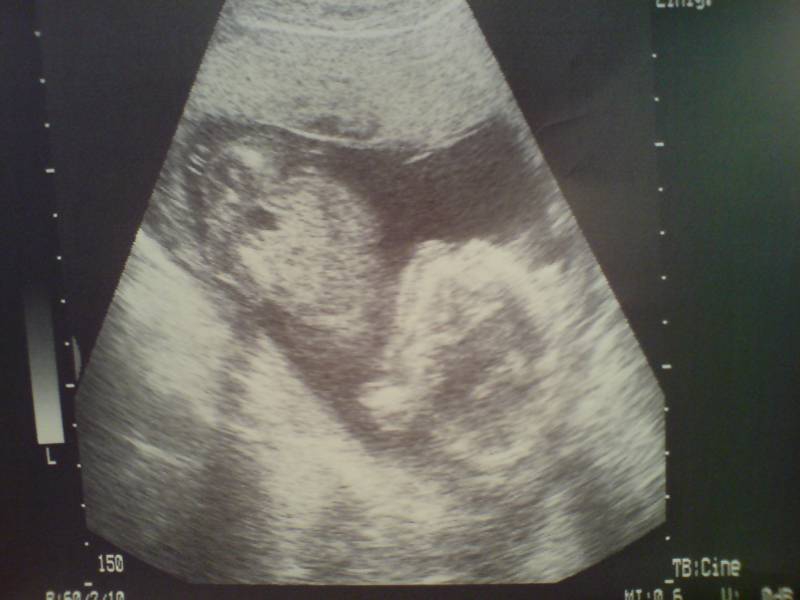

17+3 18. SSW Datum 19.05.2008 18. SSW

19+6 20. SSW Datum 19.05.2008 20. SSW